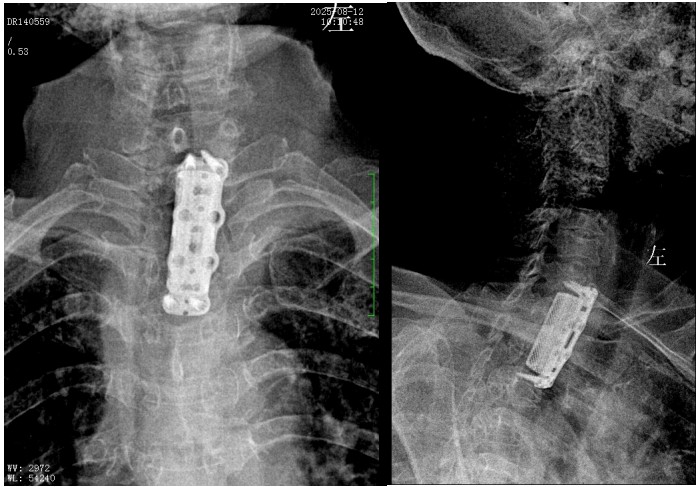

錢軍博士組織團隊進(jìn)行了詳盡的術(shù)前討論,充分的術(shù)前準(zhǔn)備后,于8月10日為患者實施了“前路病灶清除、人工椎體植入、植骨融合內(nèi)固定術(shù)”。順利完成了徹底清除病灶,椎管減壓解除脊髓壓迫,矯正后凸畸形,重建脊柱穩(wěn)定性的手術(shù)目標(biāo)。